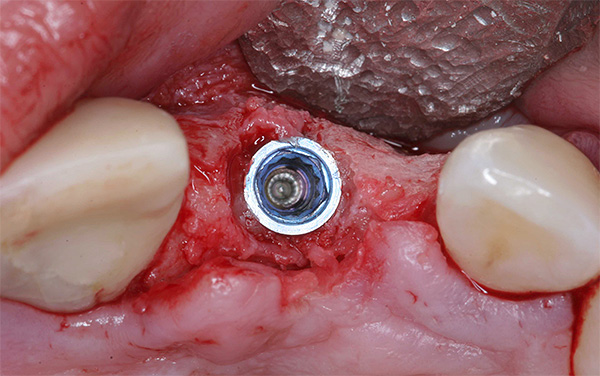

A foto abaixo mostra um exemplo de inflamação do tecido na área de um implante instalado: